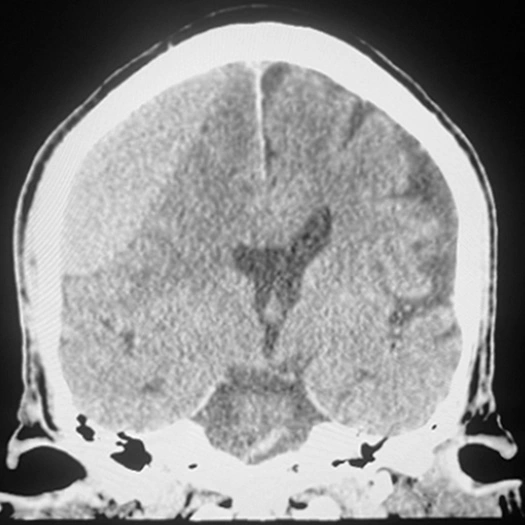

MMA Embolization

• SwiftPAC coils offered embolization

• MIDWAY 43 provided delivery support

• BENCHMARK071 provided stable, reliable access

• A combo designed to support confident, controlled delivery (see case to left)

MMA embolization with 3 SwiftPAC coils: 45 cm, 15 cm, 30 cm